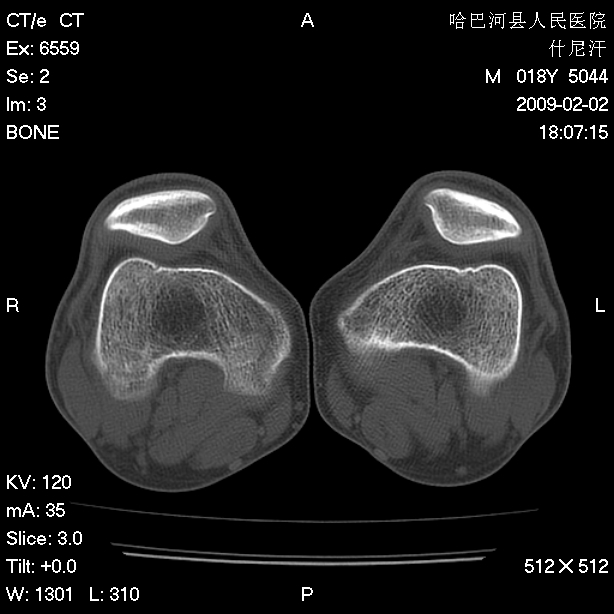

标题: CT17889:外伤后右膝关节反复疼痛3年余 [打印本页]

标题: CT17889:外伤后右膝关节反复疼痛3年余

mri检查,看看半月板情况如何。

可能韧带有问题!

ct未见明显异常。关节腔未见明显积液,半月板未见明显撕裂。但最好还是mri看看韧带及半月板情况。